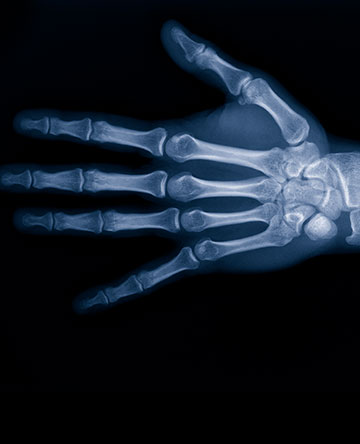

When a problem takes place in the hand, wrist, forearm or elbow, special care must be given to all the different types of tissues that make function of the upper extremity possible. Conditions may arise from trauma, athletic injury, advancing age, arthritis, or developmental processes. Many physicians at Wellington may care for these problems, and our hand surgeons are specifically trained to give that care to bones, joints, muscles, tendons, nerves, skin, and even blood vessels. Hand surgeons care for many of these problems without surgery, and they are specially trained to operate when necessary. Common surgical procedures include carpal tunnel release, hand and wrist fracture repair, trigger finger release, arthroscopy of the wrist and elbow, and arthritis procedures.

Hand surgeons are orthopedic, plastic or general surgeons who have additional fellowship training in surgery of the hand. To become a member of the American Society for Surgery of the Hand (ASSH), a hand surgeon must complete a full year of additional training and must pass a rigorous certifying examination.